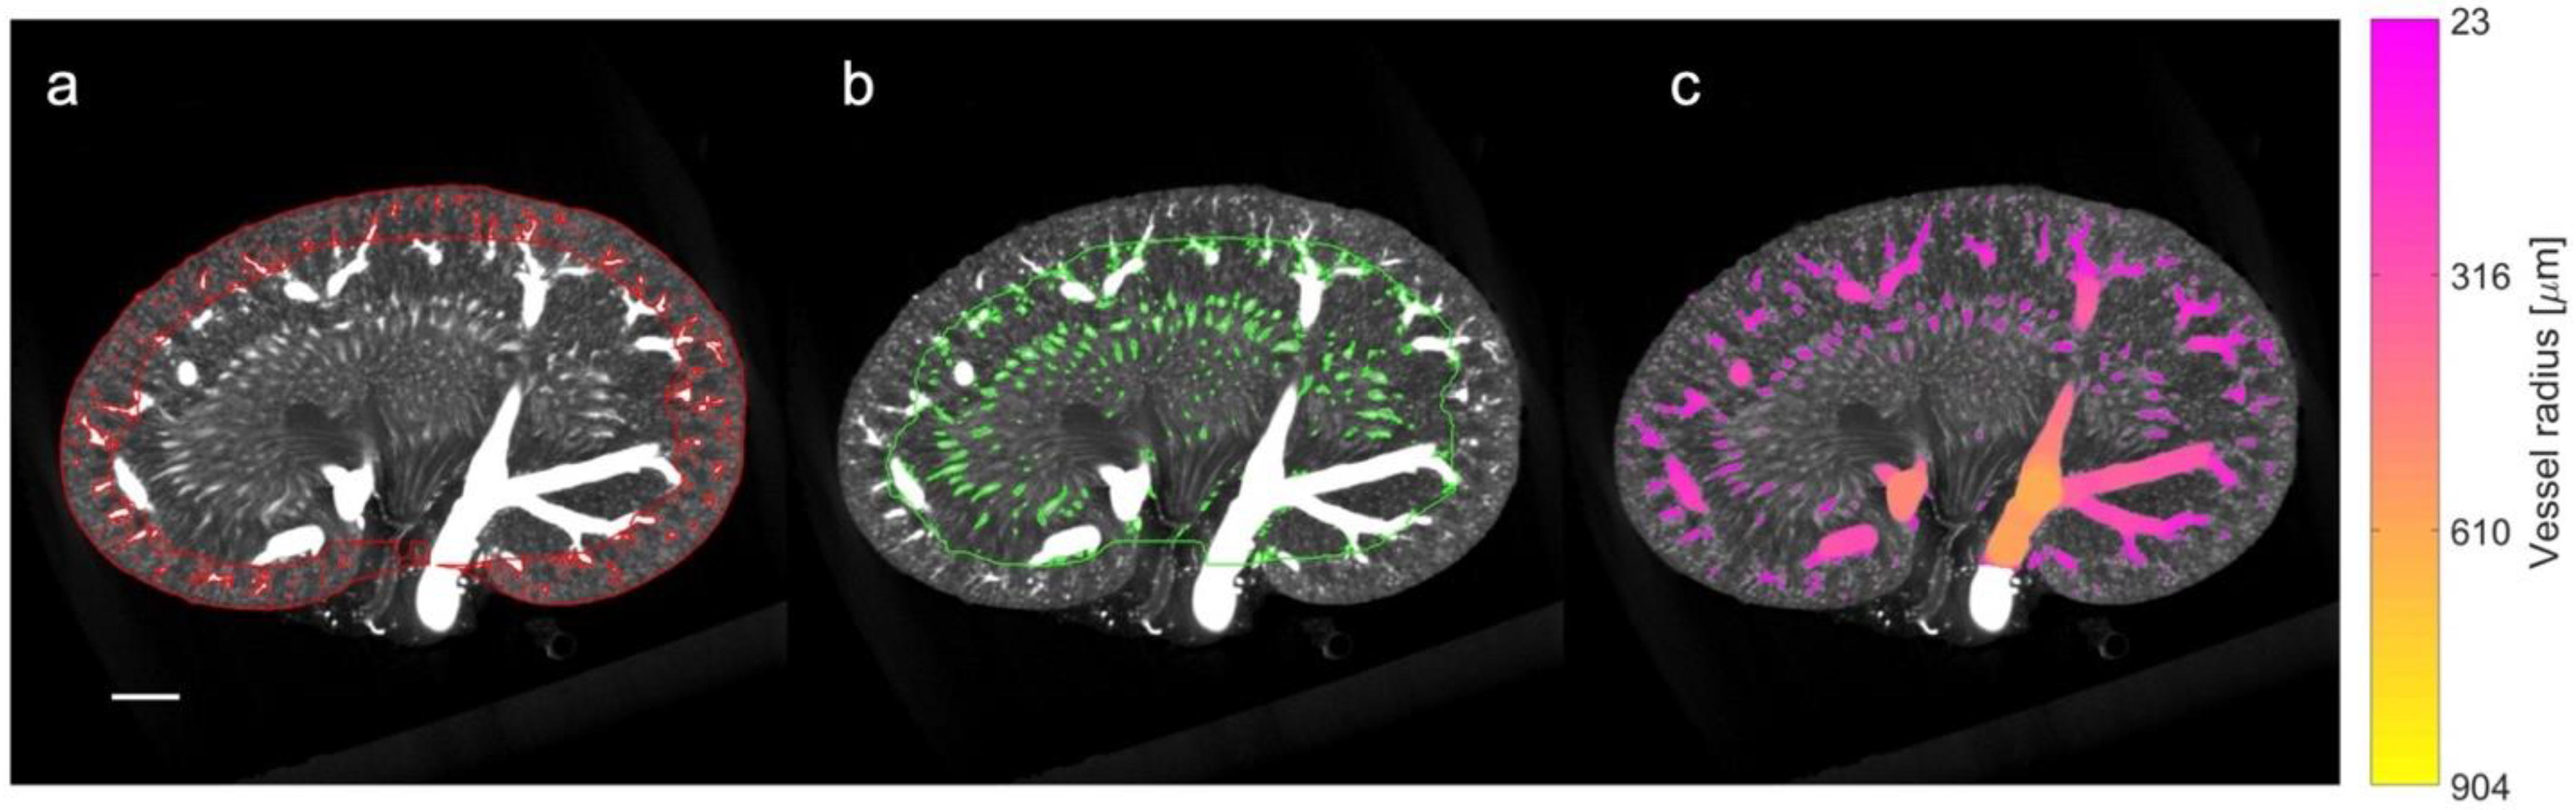

Figure 3.

µCT processing and density analysis. The coronal slice of a µCT scan is portrayed from a 22-week-old lean Zucker rat with the following: (a) the cortex defined by red borders and the mask of small vessels included in the cortical vascular density; (b) the medulla defined by the green border and the mask of small vessels included in the density analysis for the medulla region (note the exclusion of the large segmental and arcuate vessels); and (c) colored voxels representing the full vessel segmentation and the subsequent vessel radius estimation. The color indicates the local vessel radius in accordance with the colormap to the right. Size bar: 2 mm.

The density of the vessel structures was estimated separately for the cortical (Figure 3a) and medullary regions (Figure 3b) using MATLAB and calculated by taking the ratio of the vessel volume (within the region) to the full volume of the region. The analysis excludes the influence of the larger vessels, i.e., the renal artery and vein, the segmental vessels, and the arcuate vessels. This was facilitated by thresholding the estimated vessel radius map to divide the vessel segmentation into ‘small’ and ‘large’ vessel masks (Figure 3c). For the cortex region the threshold was set to a vessel radius of 10 voxels (approx. 230 µm). Similarly, for the medulla region, the threshold was set to 6 voxels (approx. 140 µm). The region of large vessels was then removed to calculate the density.

A quantitative and qualitative assessment of µCT was performed to substantiate our SRUS findings. The full volume of the µCT scans of six rats (a randomly selected subset: an LZR and a ZDF rat from each age group) were processed using ITK-snap (version 3.8.0) with the following two steps: (1) delineation of the kidney boundary and the cortex-to-medulla boundary, and (2) segmentation of the vessel structures and estimation of the local vessel radii [39]. The inner and outer medulla were combined for the µCT measurement; thus, the segmentation was performed differently than on the SRUS images, as the renal cortex was our primary focus and the segmentation on the µCT images was time-consuming. Three people completed the segmentation, two of them blinded to the type of rats to minimize performance bias. The third person could not be blinded as she was the primary investigator of the study.

The anatomical division of the kidney into the cortex and medulla regions was obtained through the following three steps. Firstly, a mask separating the kidney from the background was generated using a semi-automatic threshold-based region-growing algorithm. Manual editing was carried out when needed, e.g., to create a smooth closing at the hilum. Secondly, a mask delineating the inner part of the cortex at the arcuate vessels was created manually. In practice, approximately every fifth coronal slice was segmented using a polygon tool. The segmentation in the remaining slices was filled using label interpolation. Finally, a third mask representing the cortex region was created by ‘subtracting’ the medulla from the entire kidney mask. In the second step, an intensity threshold was manually set to segment all the vascular structures. The threshold was tuned for each scan to obtain a threshold that neither included the area between vessels (too low) nor excluded too many vessels (too high). Afterward, the local radius of the segmented vessels was estimated using the Porespy Python library [40].